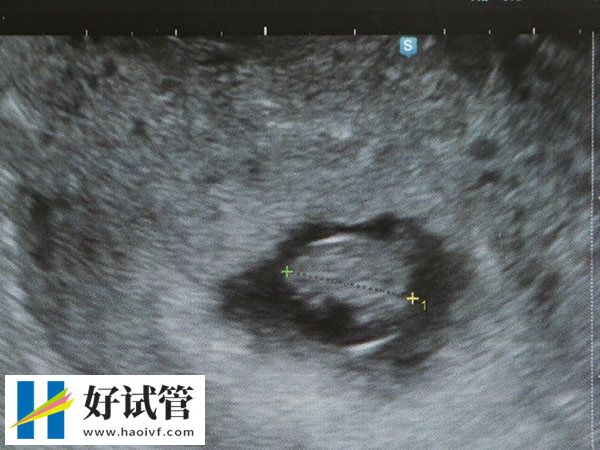

单囊胚移植是一种基于试管婴儿技术的人工受孕方式。 在这种情况下,仅将一个囊胚进行移植,而不是将多个囊胚移植到子宫腔中。这种技术通常用于那些需要削减多胎妊娠风险的状况,并避免进行多次尝试而导致精神和经济压力过大的患者。

单囊胚移植的成功率一般在55%左右,且相比于多个囊胚的移植,单囊胚移植可以在提高成功率的同时,最大程度的减少并发症的风险,传统上,通过一次移植多个囊胚的方式使得患者的多胎妊娠率提高,但同时也增加了早产和低体重儿出生等风险。因此,在目前的试管婴儿技术下,单囊胚移植已经成为一种越来越受欢迎的治疗方式。

据最近数据显示,单囊胚移植对囊胚不良率进行了更好的控制,降低了染色体异常的低遗传学风险,而且还可以提高移植成功率。 囊胚培育时间长短(5-7天)、良好的囊胚移植技术、良好的医疗体质和生育健康条件都将对单囊胚移植成功率产生有利影响。众多临床测试大量证明了单囊胚移植成功率比多囊胚移植更高。